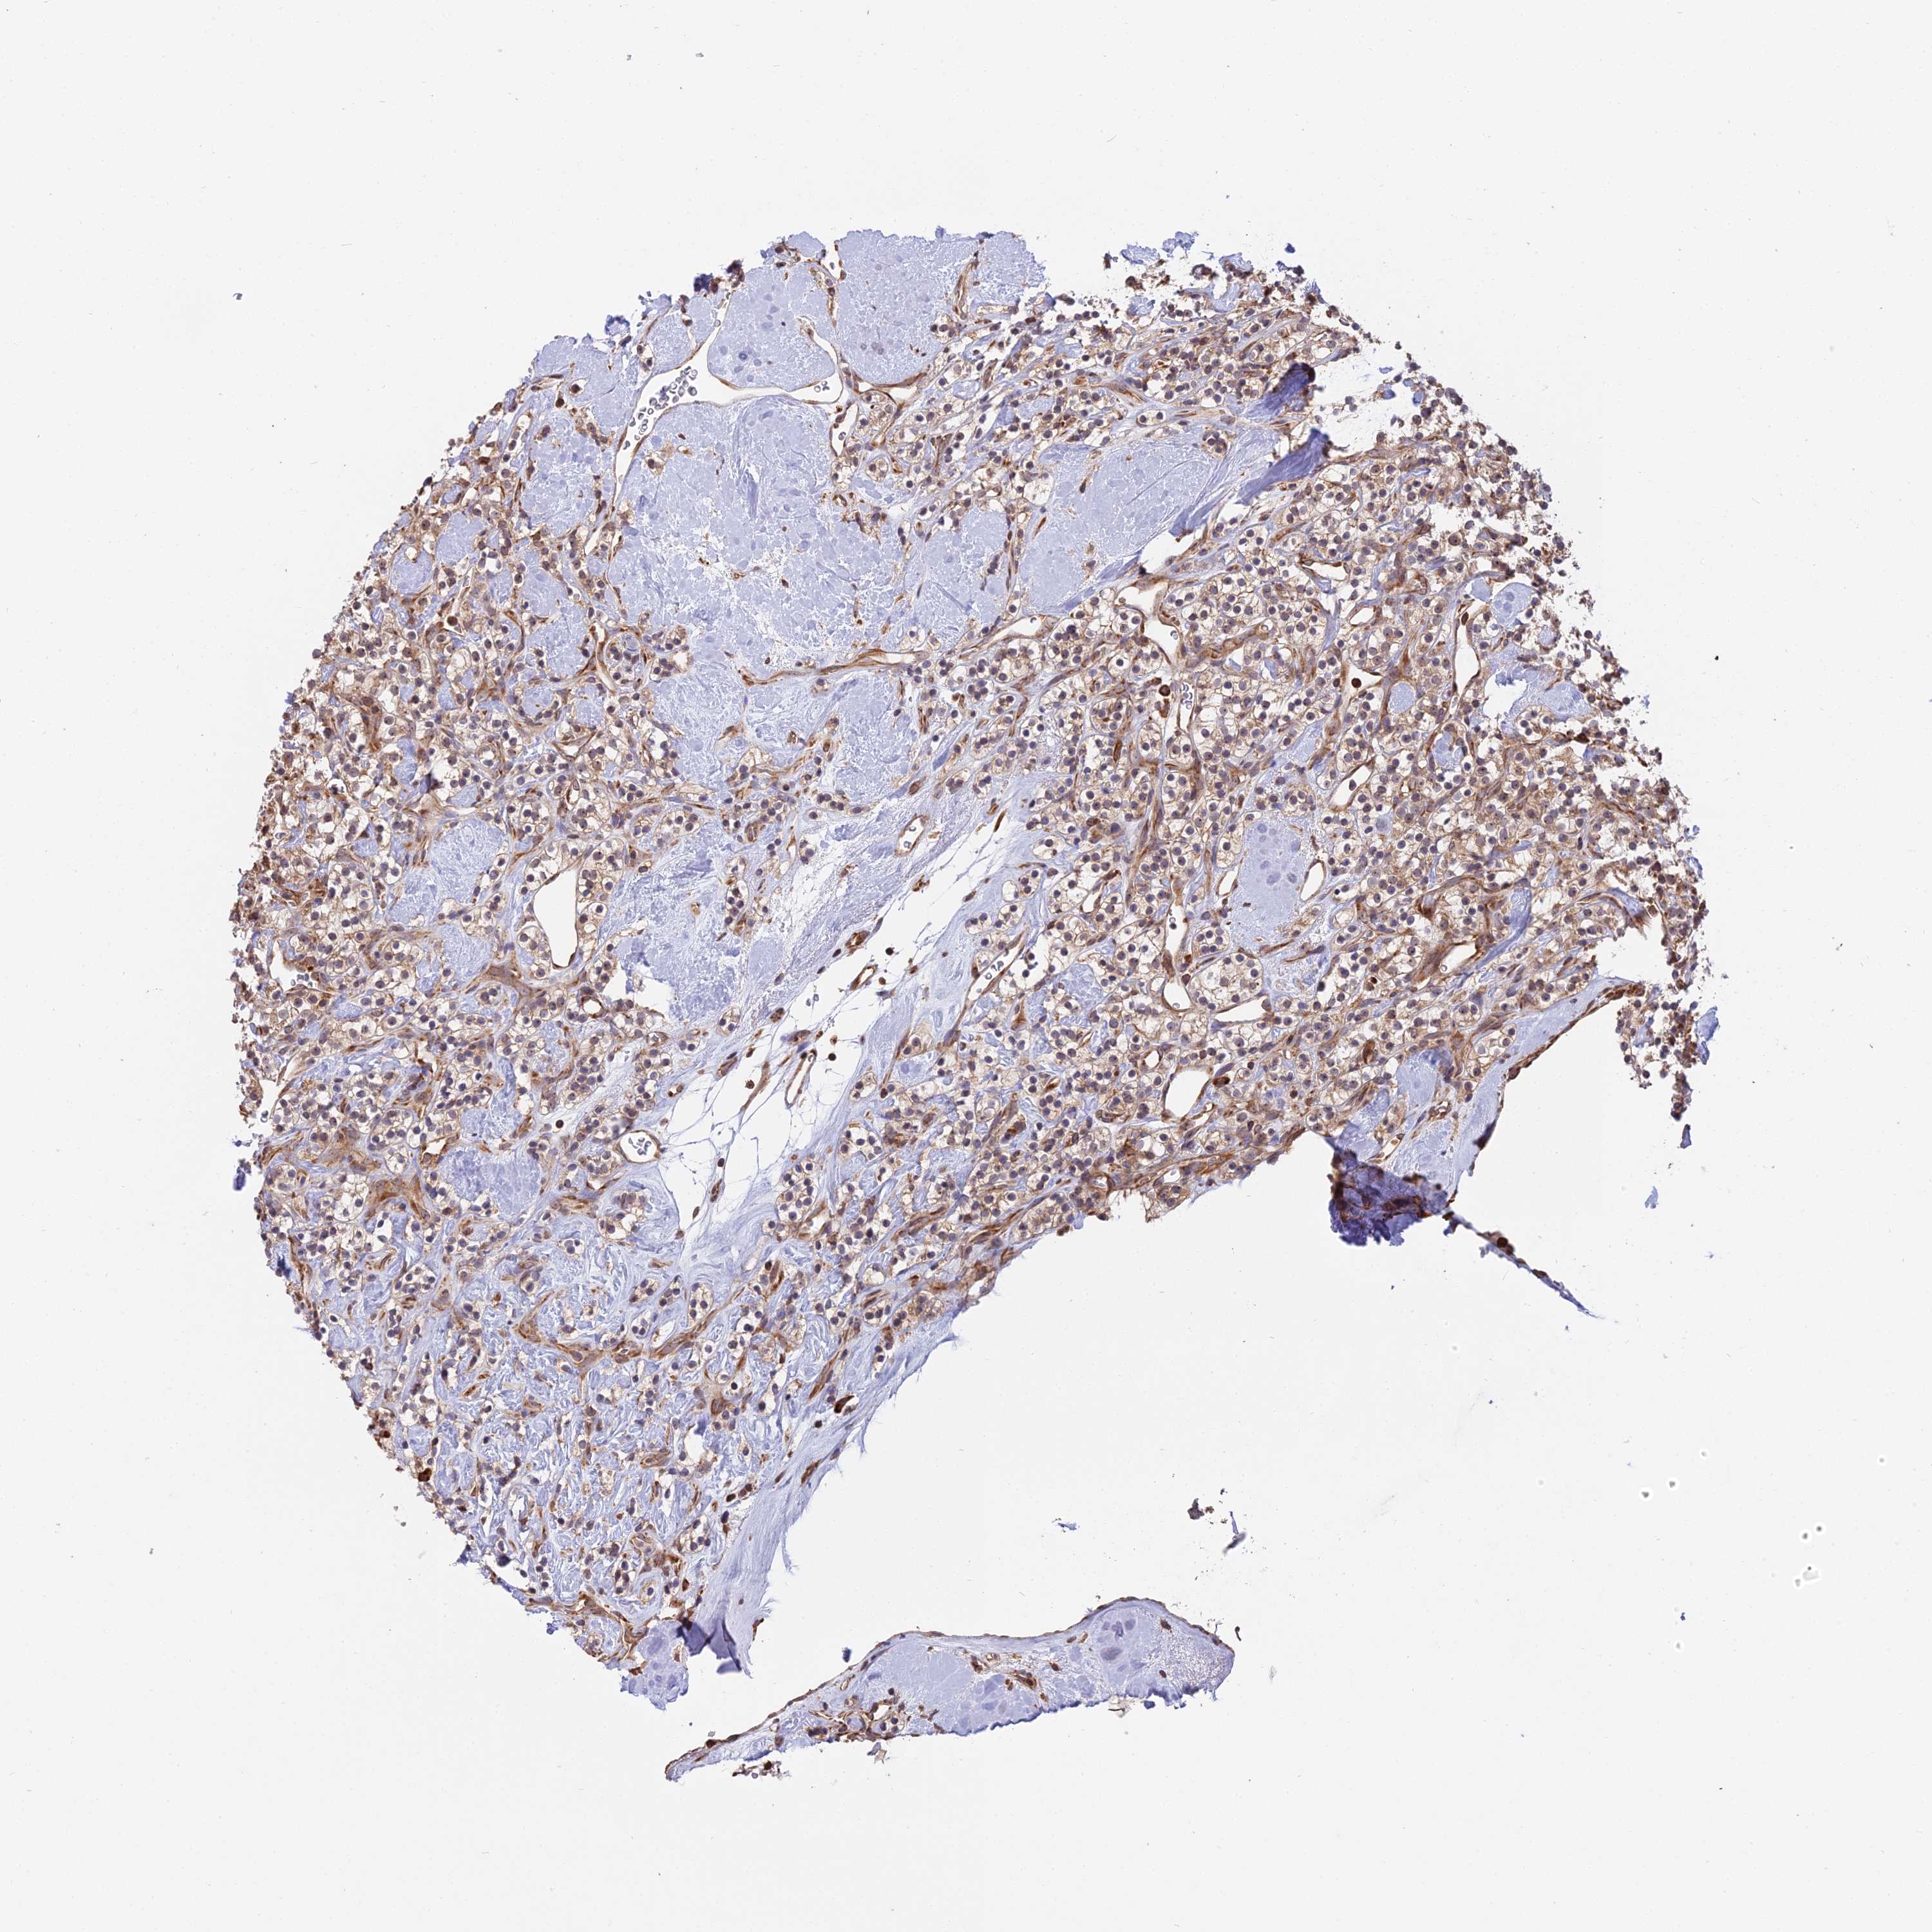

KIDNEY RENAL CLEAR CELL CARCINOMA (TCGA) - Interactive survival scatter ploti

The Survival Scatter plot shows the clinical status (i.e. dead or alive) for all individuals in the patient cohort, based on the same data that underlies the corresponding Kaplan-Meier plots. Patients that are alive at last time for follow-up are shown in blue and patients who have died during the study are shown in red.

The x-axis shows the expression levels (FPKM) of the investigated gene in the tumor tissue at the time of diagnosis. The y-axis shows the follow-up time after diagnosis (years). Both axes are complimented with kernel density curves demonstrating the data density over the axes. The top density plot shows the expression levels (FPKM) distribution among dead (red) and alive patients (blue). The right density plot shows the data density of the survived years of dead patients with high and low expression levels respectively, stratified using the cutoff indicated by the vertical dashed line through the Survival Scatter plot. This cutoff is automatically defined based on the FPKM cutoff that minimizes the p-score. The cutoff can be changed by dragging the vertical line or by entering a cutoff value in the square labeled "Current cut-off".

Under the Survival Scatter plot the p-score landscape (black curve; left axis) is shown together with dead median separation (red curve; right axis). Dead median separation is the difference in median mRNA expression between patients who have died with high and low expression, respectively. It is calculated as follows: median FPKM expression of dead patients with high expression - median FPKM expression of dead patients with low expression. This is intended to aid the user in visually exploring custom cutoffs and the associated p-scores and dead median separation.

Individual patient data is displayed and can be filtered by clicking on one or more of the category buttons on the top of the page. Categories describing expression level and patient information include: high, low, alive, dead, female, male and tumor stages. The scale of the x-axis can be toggled between linear and log-scale by clicking on the "x log" button. Mouse-over function shows TCGA ID, patient information and mRNA expression (FPKM) for each patient.

& Survival analysisi

Kaplan-Meier plots summarize results from analysis of correlation between mRNA expression level and patient survival. Patients were divided based on level of expression into one of the two groups "low" (under cut off) or "high" (over cut off). X-axis shows time for survival (years) and y-axis shows the probability of survival, where 1.0 corresponds to 100 percent.

RPL26 is potential prognostic, high expression is favorable in Kidney Renal Clear Cell Carcinoma (TCGA)

Best expression cut offi

Based on the FPKM value of each gene, patients were classified into two groups and association between prognosis (survival) and gene expression (FPKM) was examined. The best expression cut-off refers the FPKM value that yields maximal difference with regard to survival between the two groups at the lowest log-rank P-value. Best expression cut-off was selected based on survival analysis .

When clicking on this number, the vertical dashed line indicating cut-off, the interactive survival plot, and the Kaplan-Meier curve will be adjusted to show results based on the best expression cut-off.

: 1940.67

Average pTPM 2710.6

Number of samples 521